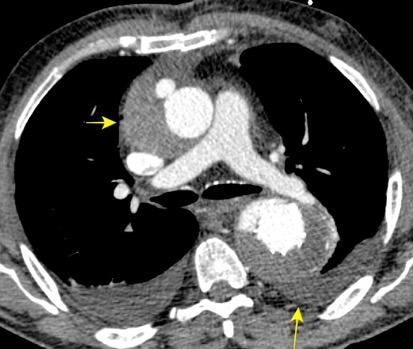

Hematoma mediastínico post-cirugía aórtica con alta densidad y derrames pleurales (densidad baja)

Mod. de Glazer HS et al. High-attenuation mediastinal masses on unenhanced CT. Radiology 1991